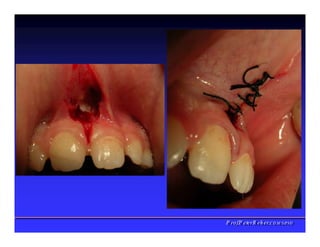

Face interna dos Lábios

✓Freios Labial

superior

✓Freio Labial

inferios

✓Bridas

Musculares